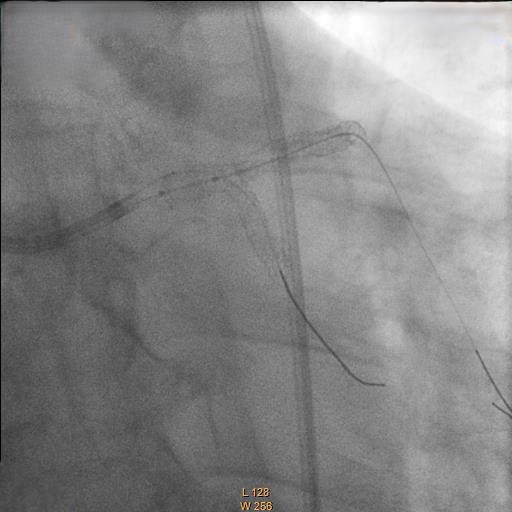

Right femoral artery punctured approach by 7Fr femoral sheath. Coronary guide catheter EBU 3.5 was used to engage left coronary artery. Percutaneous Coronary Intervention (PCI) to bifurcation Medina 1,1,1 using T and small protrusion (TAP) technique. LAD and LCX wired with workhorse wire . Mid LAD predilated with Semi-compliant (SC)2.5mm balloon and proximal LAD predilated with non-compliance (NC) 3.5mmballoon. Intravascular Ultrasound ( IVUS) was performed to measure the vessel size, lesion length and plaque morphology. Mid LAD stented with 3.5x23 mm drug eluting stent (DES). LM until proximal LAD stented with 4x33mm DES . Proximal optimization therapy (POT) at LM with NC balloon 5x8mm. Proximal LAD post dilated with NC balloon 4x20mm and mid LAD post dilated with NC balloon 3.5x15mm. LCX rewired with workhorse wire. Ostial LCX predilated with NC balloon 3.5x15mm and stented with 3.5x23mm DES subsequently post dilated with NC balloon 3.75x20mm. Final kissing balloon inflation was done at ostial LAD using NC balloon 4.0 and ostial LCX using NC balloon 3.75. Final IVUS noted double barrel sign at LM stent and confirmed with stent enhancement likely due to abluminal side branch wiring. Final POT to LM with NC balloon 5x8mm. Final IVUS showed good stent expansion and opposition with no dissection.